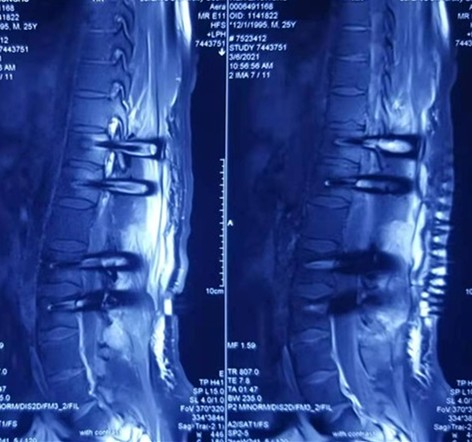

整个手术过程顺利,骨窗整齐美观,出血减少,手术视野清晰,病变组织无外渗且清理彻底,无明显副损伤,手术过程历时3小时结束,术后病人恢复良好(图片3)。

术后MRI显示肿瘤切除后术区情况良好